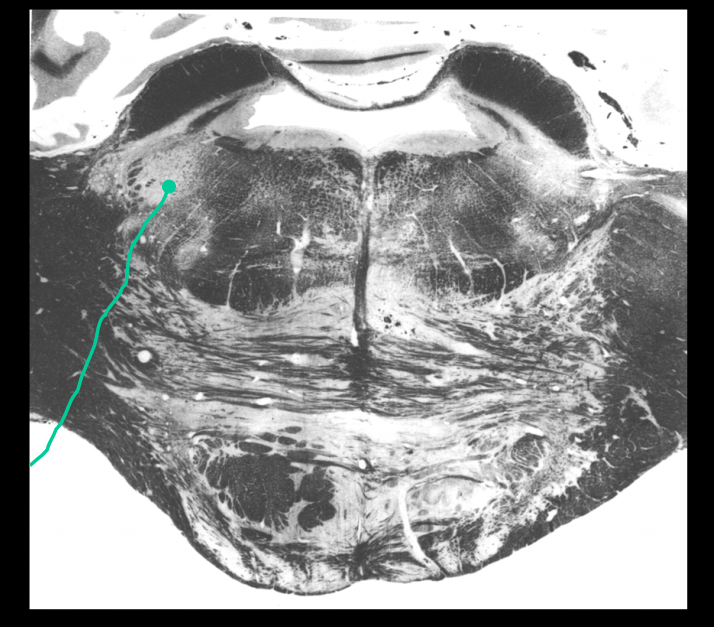

Facial motor nucleus, origin of the branchial motor (special visceral) fibers of CN VII that innervate all the muscles of facial expression, stapedius m., stylohyoid m., and posterior belly of the digastric m.

Cochlear nucleus (CN 8)